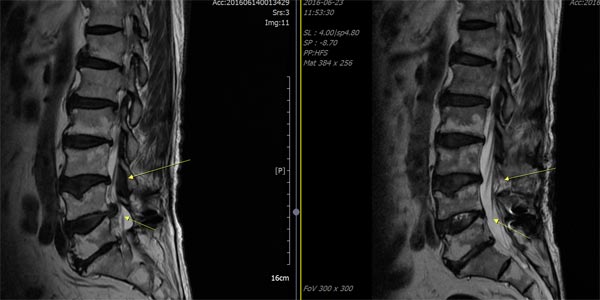

- 영상 검사: X선, MRI, CT와 같은 검사로 척추의 구조적 문제를 확인합니다. 이를 통해 신경이 얼마나 압박받고 있는지에 대한 정보를 제공합니다.

척추 협착증의 진단 방법

척추 협착증은 다양한 방법으로 진단할 수 있으며, 다음과 같은 절차를 거치게 됩니다.